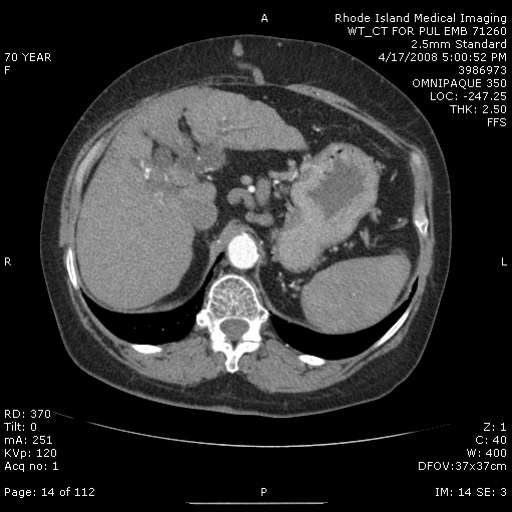

A 70-year-old woman with a history of alcoholic liver disease, peptic ulcer disease, chronic obstructive pulmonary disease (COPD) and hypothyroidism was referred for progressive dyspnea and evaluation of enlarged pulmonary arteries on chest radiograph. She had smoked approximately one pack of cigarettes daily for 40 years and developed exertional dyspnea 2-3 years earlier. At that time, she was diagnosed with COPD and inhaled bronchodilators were prescribed. She continued to smoke and her dyspnea worsened. Inhaled bronchodilators had little effect. Six months earlier she had been admitted to the hospital with Clostridium difficile colitis, gastrointestinal bleeding and COPD exacerbation. During that admission, she quit smoking and was started on supplemental oxygen therapy. A chest radiograph during the hospital stay showed cardiomegaly and large bilateral pulmonary arteries (Figure 1). Upon discharge she was referred to a pulmonologist for further evaluation. A computed tomographic pulmonary angiogram (CTPA) confirmed the presence of enlarged pulmonary arteries, but no proximal filling defects were identified (Figure 2). The lung parenchyma showed mild emphysematous changes, but no large bulla. Abdominal images revealed hepatomegaly with portal and esophageal varices (Figure 3). A transthoracic echocardiogram (TTE) found normal cardiac chamber sizes with no evidence of valvular heart disease and normal pulmonary artery pressure.

CT chest with contrast:Enlargement of the right and left main pulmonary arteries; no proximal-filling defects. No active lung disease, mild emphysematous changes without bullous emphysema. The liver is cirrhotic with evidence of esophageal and periportal varices (Figure 2).